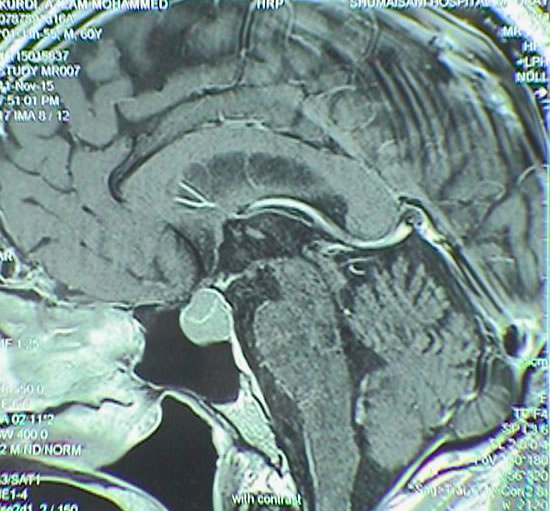

The following case demonstrate the radical resection of pituitary adenoma even with transphenoidal approach: The patient is a doctor of psychiatry 60 years old came 11-November-2015 complaining of general weakness and fainting attacks for 4 years and diagnosed as having prolactinoma. He is diabetic for 10 years with hypertension for 20 years. Signs of panhypoptuitarism were found and treated with L-thyroxin, testosterone and Dystinox 1/2 tab every 2 days. MRI sella done 29-December-2013 and repeated 14-October-2015 showing the macroadenoma is progressing in size and start to compress the optic chiasm from the left and right parasellar extension. The patient noticed visual disturbances of the left eye the last 3 months. PRL level was 6.3 µIU/ml performed 14-October-2015.

The patient was sent for investigations and MRI done 11-November-2015 showing the pituitary adenoma and the MRA showed the relation of the vascular relation to the mass.

Fig-22: The macroadenoma before surgery.

Fig-23: Intraoperative MRI confirming still having the tumor.

Fig: 24 Control MRI of the sella performed 23-December-2015 demonstrating radical resection of the pituitary adenoma. Frontal view.

Fig-25: Saggital view.